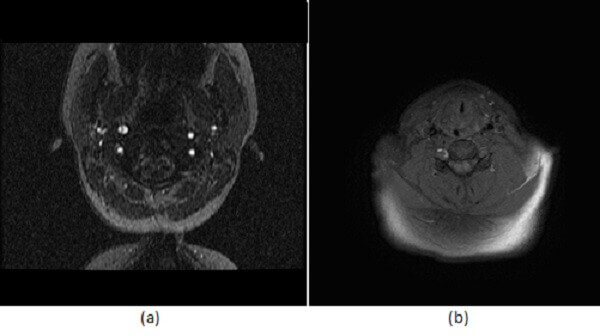

Figure 1: (a) Axial image for a time of flight MRA of the neck demonstrates an intraluminal flap within the cervical portion of the right internal carotid. (b) Fat saturated T1 image at the same level demonstrates a crescentic T1 hyperintensity consistent with subacute intramural hematoma. These finding are consistent with a dissection .

When using MRA to evaluate dissection, be sure to add a T1 fat saturated sequence through the neck. This sequence is optimized to detect a pathognomonic sign of dissection – intramural hematoma – which manifests as a crescentic T1 hyperintensity around the vessel (a region typically dark on a fat saturated sequences). Two pitfalls to the use of MRA in the evaluation of dissection include a false positive when incomplete fat saturation simulates a hematoma (look for the finding on the asymptomatic side) and a false negative in hyperacute dissection, which is not hyper intense on T1.